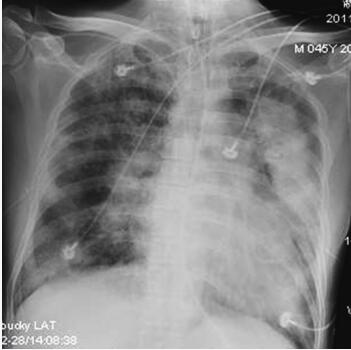

诊治经过:应用亚胺培南-西司他汀钠0.5g,每8小时1次静脉滴注、利奈唑胺0.6g,每12小时1次,静脉滴注联合抗感染,纤维支气管镜反复吸痰,适当控制液体量、减轻心脏负荷治疗。床边超声心动图示主动脉瓣二叶式畸形、主动脉瓣中度狭窄伴轻度反流,左心肥大,二尖瓣中度反流,三尖瓣轻至中度反流,中度肺动脉高压,EF 55%。经治6天后患者全身毒血症状有所减轻,氧合功能改善(机械通气下FiO2 45%,PEEP 5cmH2O,SPO2 96%),全身感染及心功能相关指标较入笔者医院时好转(2月22日:WBC 16.8×109/L,CRP 75.3mg/L,NT-ProBNP 4462pg/ml;2月28日:WBC 12.7×109/L,CRP 29.8mg/L,氨基酸B型利钠肽原NT-ProBNP 2222pg/ml)。但体温仍在38.5℃左右波动,床边胸片(2月28日):两肺广泛感染病灶,较2月22日胸片似有吸收(图63-3)。

图63-3 起病第25天(入笔者医院第7天)两肺感染病灶较入笔者医院当天略见吸收

患者于3月2日晚突然出现心率上升、氧合及血压下降(P 130~180次/分、SPO2低至85%、BP低至80/50mmHg),予镇静、上调呼吸机支持力度及补液1000ml后情况缓解,当晚体温最高上升至39.2℃。3月3日血液检查见WBC、 CRP及NT-ProBNP较3天前大幅上升(WBC 15.9×109/L,CRP 106.3mg/L,NT-ProBNP 4973pg/ml)。多次血、CVP导管、胸腔积液培养结果均阴性,多次痰培养结果均示鲍曼不动杆菌(+++),仅多黏菌素敏感。复查胸部CT:双肺广泛渗出、坏死病变,较2月23日略有进展(图63-4)。

图63-4 起病第27天(入笔者医院第9天)CT示双肺广泛渗出、坏死病变有进展

3月4日体温骤高至39.5℃,两日来心率持续波动于130~140次/分,全身感染及心功能相关指标进一步上升(WBC 18.8×109/L,CRP 112.5mg/L,NT-ProBNP 6620pg/ml)。经笔者医院感染科会诊,遂加用伏立康唑0.4g,每12小时1次静脉滴注抗真菌,甲泼尼龙40mg,每日1次静脉滴注促进肺部坏死组织吸收。至傍晚患者出现心率减慢、血压下降,氧饱和度下降,予补液、强心、升压等治疗后未见好转。床边胸片:双肺广泛感染灶(图63-5)。之后出现心脏骤停,经持续近3小时的心肺复苏无效,最终死亡。

图63-5 起病第29天(入笔者医院第11天)胸片示两肺广泛感染病灶